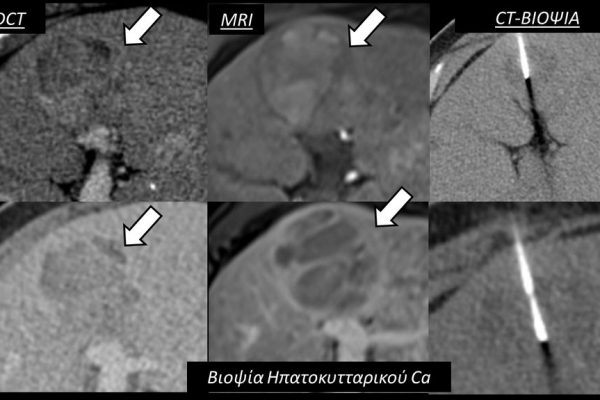

Η διαδερμική βιοψία είναι μία ελάχιστα επεμβατική μέθοδος λήψης υλικού από τον όγκο για κυτταρολογική και ιστολογική εξέταση, από εστιακές αλλοιώσεις του ήπατος, πνεύμονα, νεφρού κλπ. Συστήνεται από τον κλινικό ιατρό ανάλογα με το είδος και το μέγεθος της βλάβης και πραγματοποιείται με ασφάλεια από επεμβατικό ακτινολόγο με την καθοδήγηση αξονικού τομογράφου ή υπερήχων. Στη σύγχρονη ογκολογική θεραπεία όπου γίνεται προσπάθεια καταπολέμησης του καρκίνου σε μοριακό επίπεδο κρίνεται αναγκαία η ακριβής ιστολογική ταυτοποίηση του όγκου ώστε να εφαρμοσθεί εξατομικευμένη θεραπεία για το βέλτιστο αποτέλεσμα. Οι κατευθυνόμενες βιοψίες στοχευουν στο να παρέχουν στον κλινικό ογκολόγο το απαραίτο ιστοπαθολογικό υλικό που θα του επιτρέψει να εφαρμόσει την κατάλληλη θεραπεία για τον ογκολογικό ασθενή.